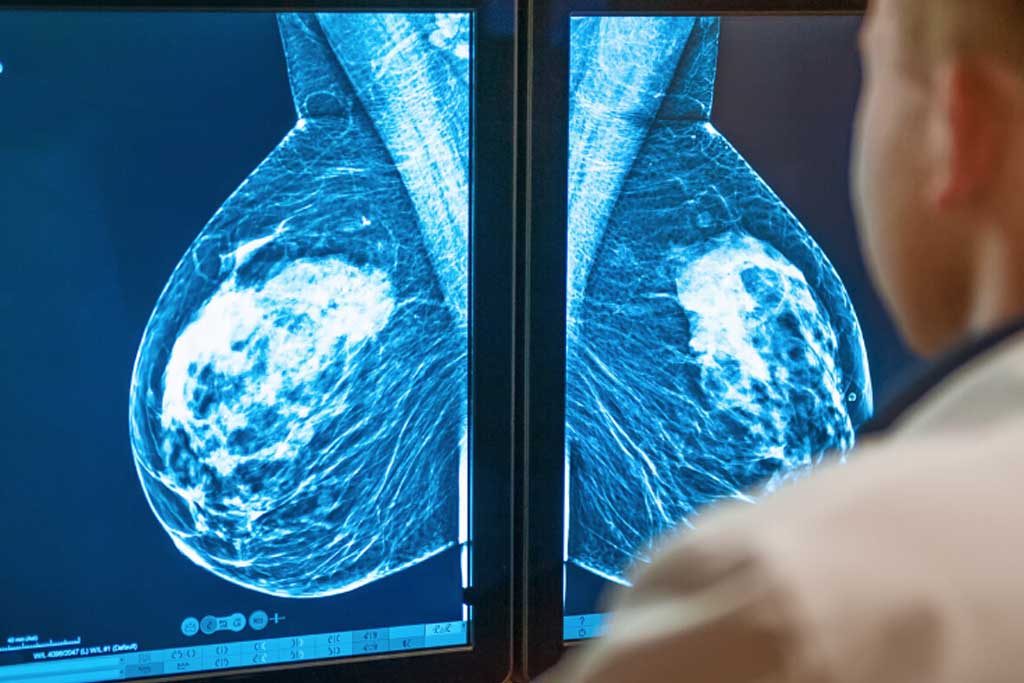

ماموگرافی سینه و زیربغل ستون اصلی غربالگری سرطان پستان است؛ روشی که میتواند تغییرات بسیار ریز بافتی را قبل از بروز علائم قابل لمس یا دیداری آشکار کند و احتمال نجات جان بیمار را افزایش دهد. در نمای استاندارد، علاوه بر بافت پستان، بخشهایی از ناحیه زیربغل (دم پستان/غدد لنفاوی آکزیلاری) نیز در کادر قرار میگیرد؛ بنابراین «ماموگرافی سینه و زیربغل» نام دقیقی برای توصیف هدف اصلی این تصویربرداری است: کشف زودهنگام تغییرات پستان و ارزیابی اولیه ناحیه زیربغل که میتواند درگیر تودهها یا بزرگشدگی غدد لنفاوی باشد. مطالعات متعدد نشان دادهاند که انجام منظم ماموگرافی، مرگومیر ناشی از سرطان پستان را کاهش میدهد

ماموگرافی نوعی تصویربرداری با اشعه ایکسِ کمدوز از پستان است. هدف اصلی در غربالگری، پیدا کردن سرطانهای پنهان در زنانی است که هیچ علامتی ندارند. اگر قبلاً یافتهای در معاینه یا تصویر دیده شده باشد (مثلاً توده یا فرورفتگی پوست یا ترشح خودبهخودی از نوک سینه)، انجام ماموگرافی تشخیصی همراه با تصاویر تکمیلی و گاهی سونوگرافی پستان برای ارزیابی دقیقتر توصیه میشود.

در ماموگرافی غربالگری، از هر پستان حداقل دو نما گرفته میشود: کرانیوکودال (CC) و مدیولترال اُبلیک (MLO). نمای MLO بهطور اختصاصی بخشی از بافت پستان که به سمت زیربغل کشیده میشود و همچنین غدد لنفاوی آکزیلاری را بهتر در بر میگیرد. به همین دلیل در بسیاری از مراکز، تکنسین میکوشد موقعیتدهی را طوری انجام دهد که «دم پستان» و نواحی زیربغل در تصویر واضح باشند. این همان چیزی است که در راهنمای بیمار نیز یادآوری میشود: یک نما از بالا به پایین و دیگری از طرفین تا ناحیه زیربغل گرفته میشود تا ارزیابی کاملتری داشته باشیم.